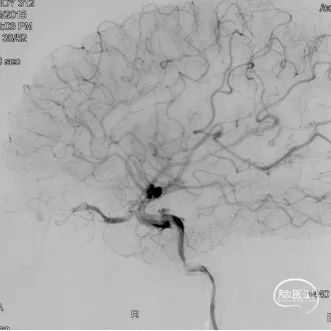

术前造影

双侧颈内动脉正侧位造影见前颅窝底硬脑膜动静脉瘘,双侧筛前动脉、筛后动脉向瘘口供血,通过皮层静脉向上矢状窦引流。

双侧颈外动脉正侧位造影见镰前动脉向瘘口供血。

左侧椎动脉正侧位造影未见明显异常。